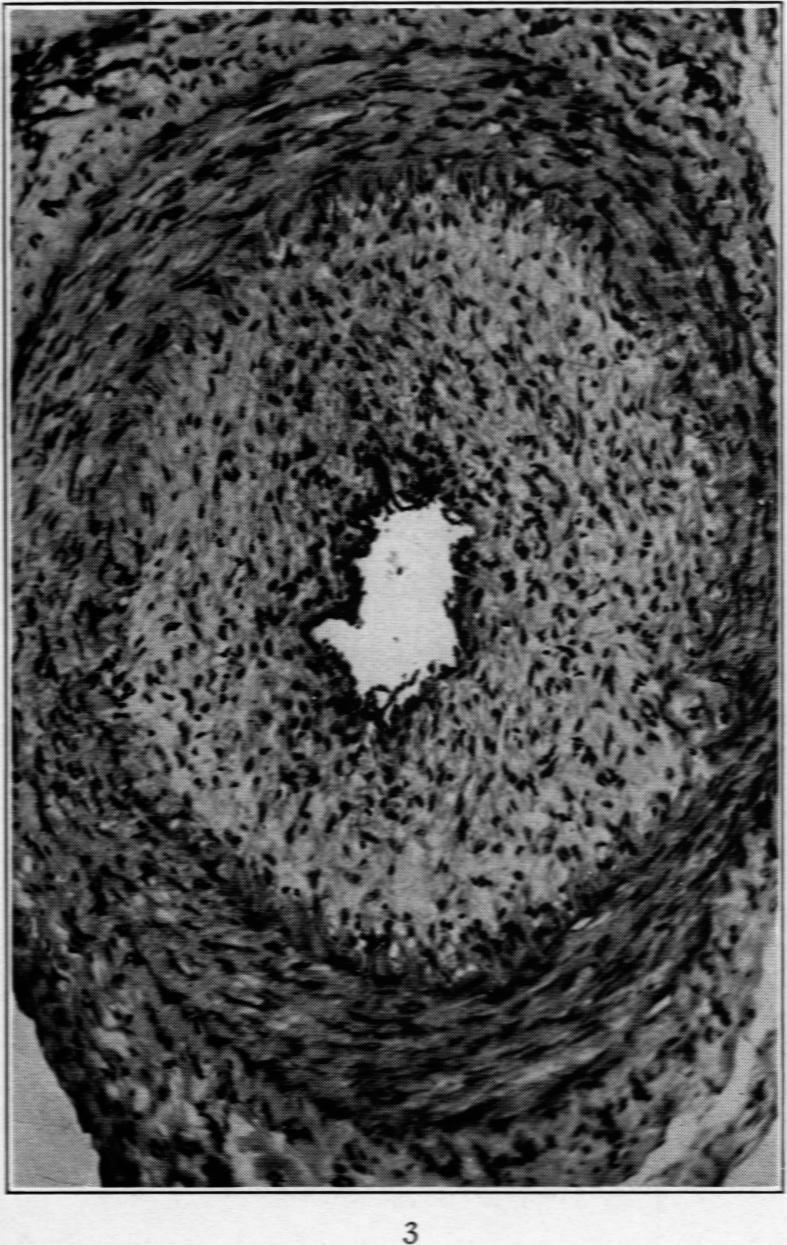

A Clinical and Pathological Study of Periarteritis Nodosa: A Report of Five Cases, One Histologically Healed.

Am J Pathol. 1930 Jul;6(4):401-426.5.